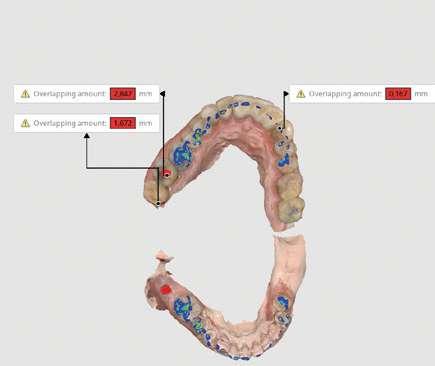

 Expansión confirmada mediante superposición de los modelos maxilares digitales previos y posteriores al tratamiento mediante MARPE (Ilustración 6). Se obtuvo un aumento transversal del 5,14 mm a nivel de los primeros molares.

Fase 2: corrección con alineadores Una vez corregida la discrepancia transversal y finalizado el periodo de control, el tratamiento continuó con alineadores Spark™, con un protocolo de uso de 22 horas diarias y cambios de alineadores cada 10 días. El tratamiento con alineadores se planificó en 2 etapas. Una primera etapa para abordar el plano vertical y una etapa final para abordar el plano sagital.

Corrección vertical (Ilustración 7):

 Extrusión de incisivos superiores (1,7 mm) e inferiores (1,5 mm) con attachments de control radicular.

 Intrusión de molares mandibulares mediante turbo bites para facilitar el cierre de la mordida.

Ilustración 6. Superposición del modelo inicial (azul) modelo y post-disyunción (gris).

Ilustración 7. Fotografías iniciales, post-disyunción e intra-tratamiento tras el 1º set de alineadores Spark™ (corrección vertical).